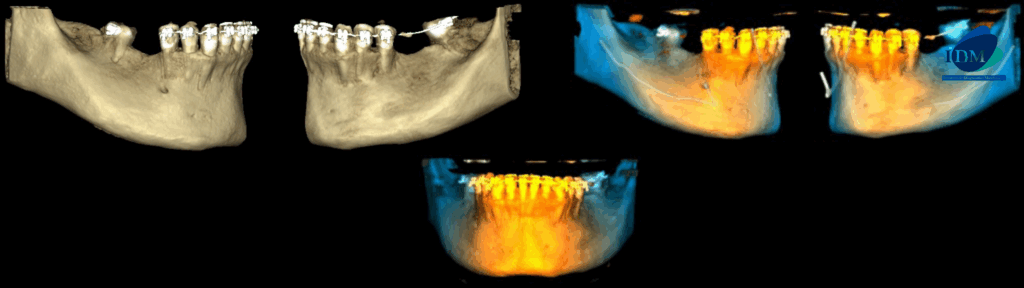

RECONSTRUCCIÓN 3D